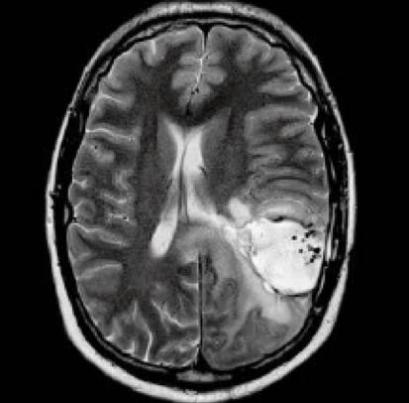

(3)脑血管病手术,如海绵状血管瘤、脑动静脉畸形等,有部分位于深部,且肿瘤微小,应用iMRI,结合术中实时导航,可有效解决病变漂移,精确定位病变。